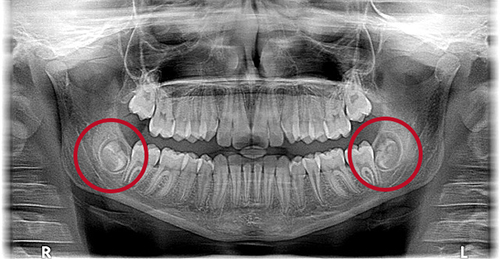

사랑니는 살면서 크게 문제가 없는 경우도 있지만 어쩔 수 없이 발치해야 하는 상황이 올 수도 있습니다. 사랑니 특성상 위치가 깊숙한 곳에 자리 잡아있기 때문에 발치 후 주의사항을 총정리해 보았습니다.

사랑니는 주로 어금니 제일 안쪽에 위치한 이빨이고 또 일반 치아와는 달리 치아가 자라나는 방향이 제각기 일 수가 있어 발치 시에는 필요에 따라 잇몸을 절개해야 할 수도 있습니다. 이런 경우 잇몸 절개와 발치에 따른 출혈이 동반되는데, 발치 후에는 거즈를 꼭 물고 2시간 동안 지혈을 제대로 해야 합니다.